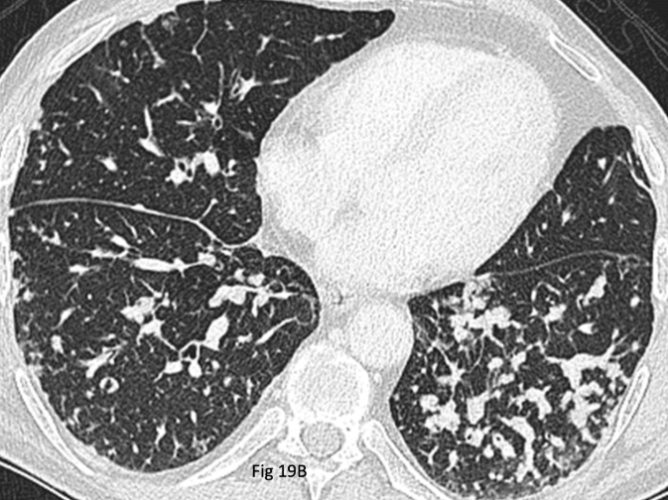

磨玻璃樣肺結節(GGO)特別在哪?

對於風險低的肺結節(小的、影像特徵良性的、沒有危險因子的),定期用低劑量CT追蹤是最標準、也最常採用的「肺結節治療」方法。為什麼?因為大部分是良性的,不會變也不會害你。追蹤的目的在於監視它有無變化:變大了?實質成分增加了?形態變差了?如果追蹤一兩年都沒變化(特別是實心小結節),那基本可以放心是良性的。追蹤的間隔(3個月、6個月、1年、2年)由醫師根據初始風險評估來決定。磨玻璃結節的追蹤期通常會更長(可能長達5年),因為它們變化慢。耐心配合追蹤是非常關鍵的「肺結節治療」手段。

這特別適用於純磨玻璃結節(pGGO)或實質成分很少的混合型磨玻璃結節(mGGO),尤其當它很小(